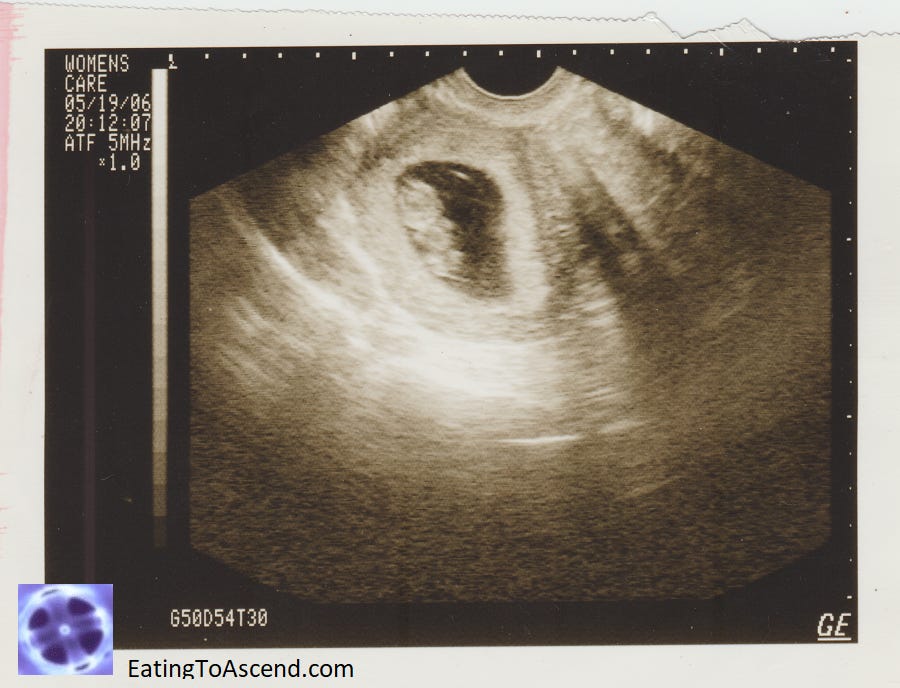

The sonogram image of this mystery child was a sign given to me in the same obscure shop less than two weeks after finding the doll and less than two days after the Democratic National Convention-hosted abortions. I walked into the thrift shop’s small, stacked-floor-to-ceiling book room, and directly to my right at eye level was this small pieve of paper sitting on the shelf, obviously fallen out of or taken from a donated book. It struck my heart like a lightningbolt, for it was clear to see the baby’s head, arms, hands and feet, and I wondered if it was alive or dead, the date on it 2006 – a year younger than my oldest granddaughter, Emily. With care I placed it in between pages of the notebook I carry in my ‘purse’ (for want of a better term, a satchel, for I am certainly not fashionable, an anathematic word in the first place as the only One I want to fashion me is YHVH). As I drove ‘home’, I felt something gestating spiritually.